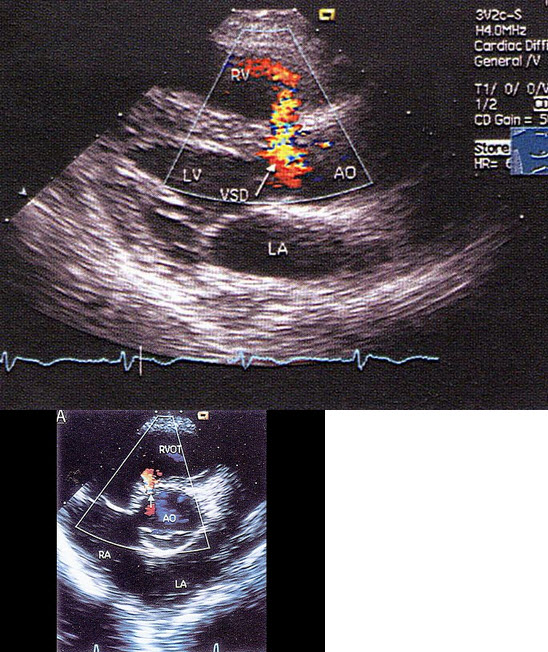

54、单项选择题

某患者左室长轴切面超声心动图如图所示,诊断为()